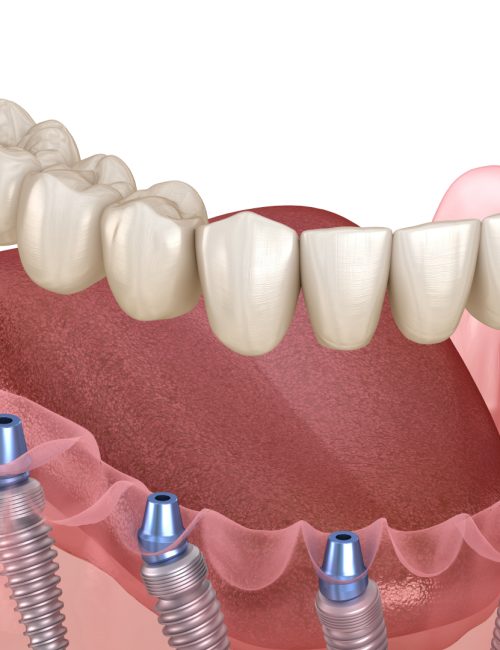

Caratteristiche dell’implantologia All on 8

Protesi fissa su 8 impianti comprende una arcata circolare su impianti. Adatta per i pazienti affetti da mancanza totale dei denti per arcata, che ricercano la serenità di riacquisire un sorriso e una bocca perfettamente naturale.